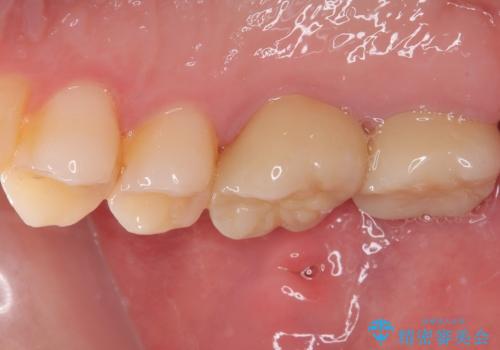

上顎は仮歯に置き換えた後に、それまでの痛みは一切感じなくなり、下顎も一度目の根管治療で痛みを感じることはなくなりました。

根管治療を行った歯の周辺にある病変は数ヶ月後にレントゲン写真を撮って確認する必要があるため、今後経過観察を行っていく予定です。